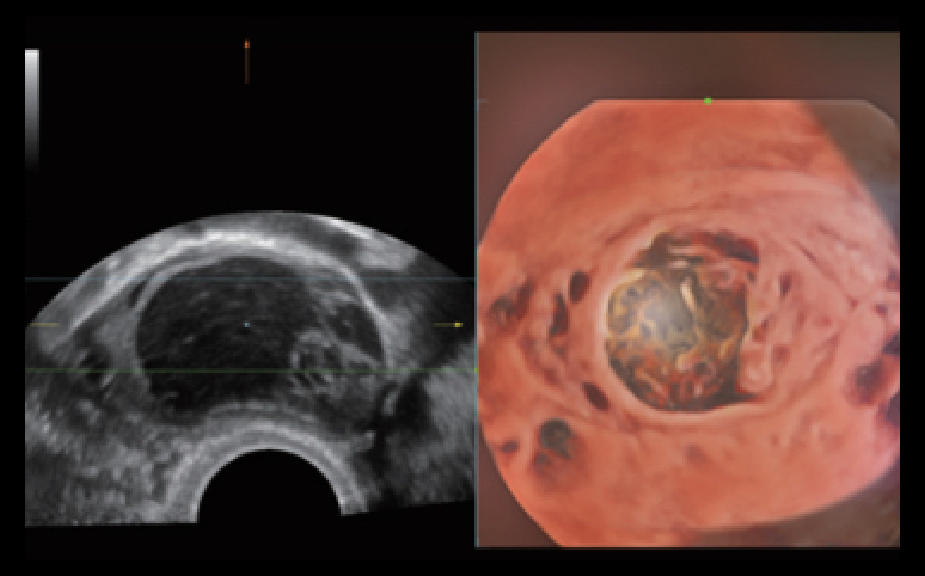

Nuewa I9, kad?nlara ve yenido?anlara y?nelik sa?l?k hizmetleri i?in ?zel olarak tasarlam??t?r ve i?ten d??a yenilik?i bir deneyim sunmaktad?r. Bu yenilikler, karma??k klinik senaryolara ili?kin derinlemesine bilgilere dayal? olarak geli?tirilmi?tir ayr?ca do?ru ve zaman?nda yan?tlar?n yan? s?ra, ola?an├╝st├╝ verimlilik ve ola?an├╝st├╝ kullan?c? deneyimi sunar.

ZST + Taraf?ndan Desteklenen Eksiksiz ??z├╝m

ZST+ platformu, ultrason evrimini temsil eden ola?an├╝st├╝ bir yeniliktir. Ultrason ?l?├╝mlerini geleneksel ???n bi?imlendirmeden kanal verilerine dayal? i?lemeye d?n├╝?t├╝r├╝r. Mekansal ??z├╝n├╝rl├╝k, zamansal ??z├╝n├╝rl├╝k ve doku homojenli?i aras?ndaki geleneksel dengeli s?n?rlaman?n ├╝stesinden gelir ve kesintisiz iyile?tirmelerle s?n?rs?z g?r├╝nt├╝leme ??z├╝mleri i?in ola?an├╝st├╝ g?r├╝nt├╝ kalitesi sunar.